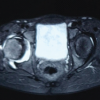

A twelve year old boy presented to us with a history of a gradually enlarging mass in the left popliteal fossa since eighteen months. He complained of restriction of terminal knee flexion, but he had no pain. On general examination our patient had cutaneous lentiges over the back of the neck and on the skin over the back of left knee. Local examination revealed a palpable mass around 10cms in diameter and about 3 cms raised from the surrounding tissues occupying the entire popliteal fossa. The mass was not warm or tender and was not associated with any skin changes. It was non- pulsatile. The flexion of the left knee was terminally restricted as compared to the right knee. The anteroposterior and lateral radiographs of the knee were normal. Magnetic resonance imaging revealed a well defined lobulated STIR/ T2 hyperintense lesion measuring 12.8 x 4.8 x 8.8 cms with multiple thick septae within it. Superioly, the lesion was lying in the soft tissue between semimembrinosus, gracilis and sartorius muscles posteriorly and gastrocnemius muscle anteriorly. Inferiorly it was lying posterior to gastrocnemius muscle. The lesion was lying posterior to neurovascular structures in the popliteal fossa. There was minimal effusion within the joint which was thought to be sympathetic in nature. The mass was interpreted as being either a complicated popliteal cyst or chronic hematoma without ruling out the possibility of soft tissue sarcoma. We decided to perform an open excisional biopsy of the lesion which revealed a reddish-brown cystic-nodular mass. The mass was seen to communicate with the knee joint. The cyst was removed and sent for histopatholoical examination. The communication with the knee joint space was sealed with purse-string sutures. The histology revealed papillary projections lined by hyperplasic synovial cells infiltrated by lymphocytes and few plasma cells with hemosiderin deposits and was consistent with a histology of pigmented villonodular synovitis. As we suspected that the disease had originated in the knee and spread to the popliteal space, the first surgery (posterior only) could not have removed the intra-articular origin of the lesion. So we decided to do arthroscopic synovectomy. We performed an arthroscopic synovectomy 3 weeks later. Brownish-red hypertrophied synovium with papillary projections was found in all compartments of the knee was removed and sent for histological examination. The histology from the intra-articular lesion was also consistent with a diagnosis of pigmented villonodular synovitis. At 6 months follow-up, there is no relapse.